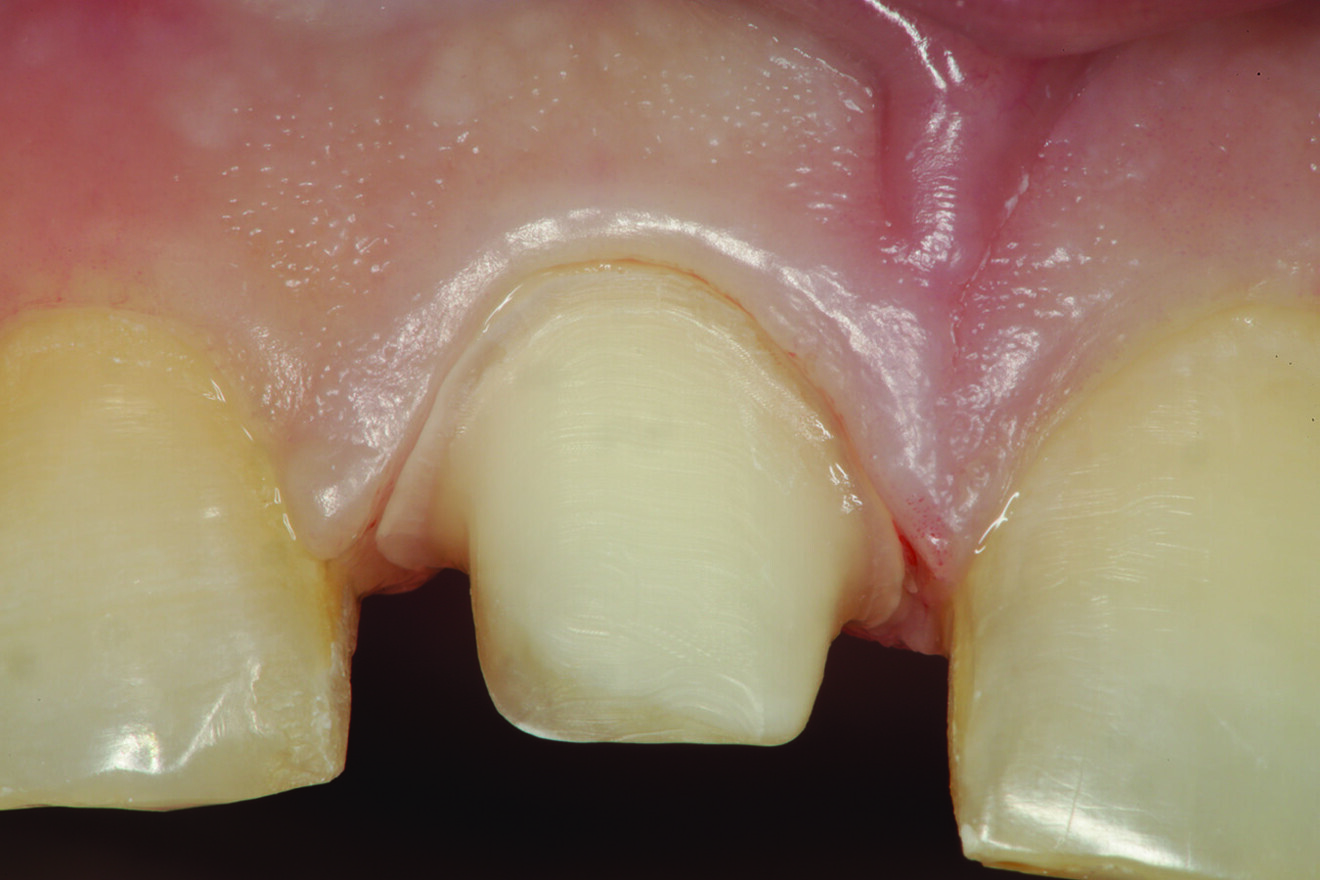

Fig. 13: Incisal view of the retracted preparation after the gingivoplasty had been completed.